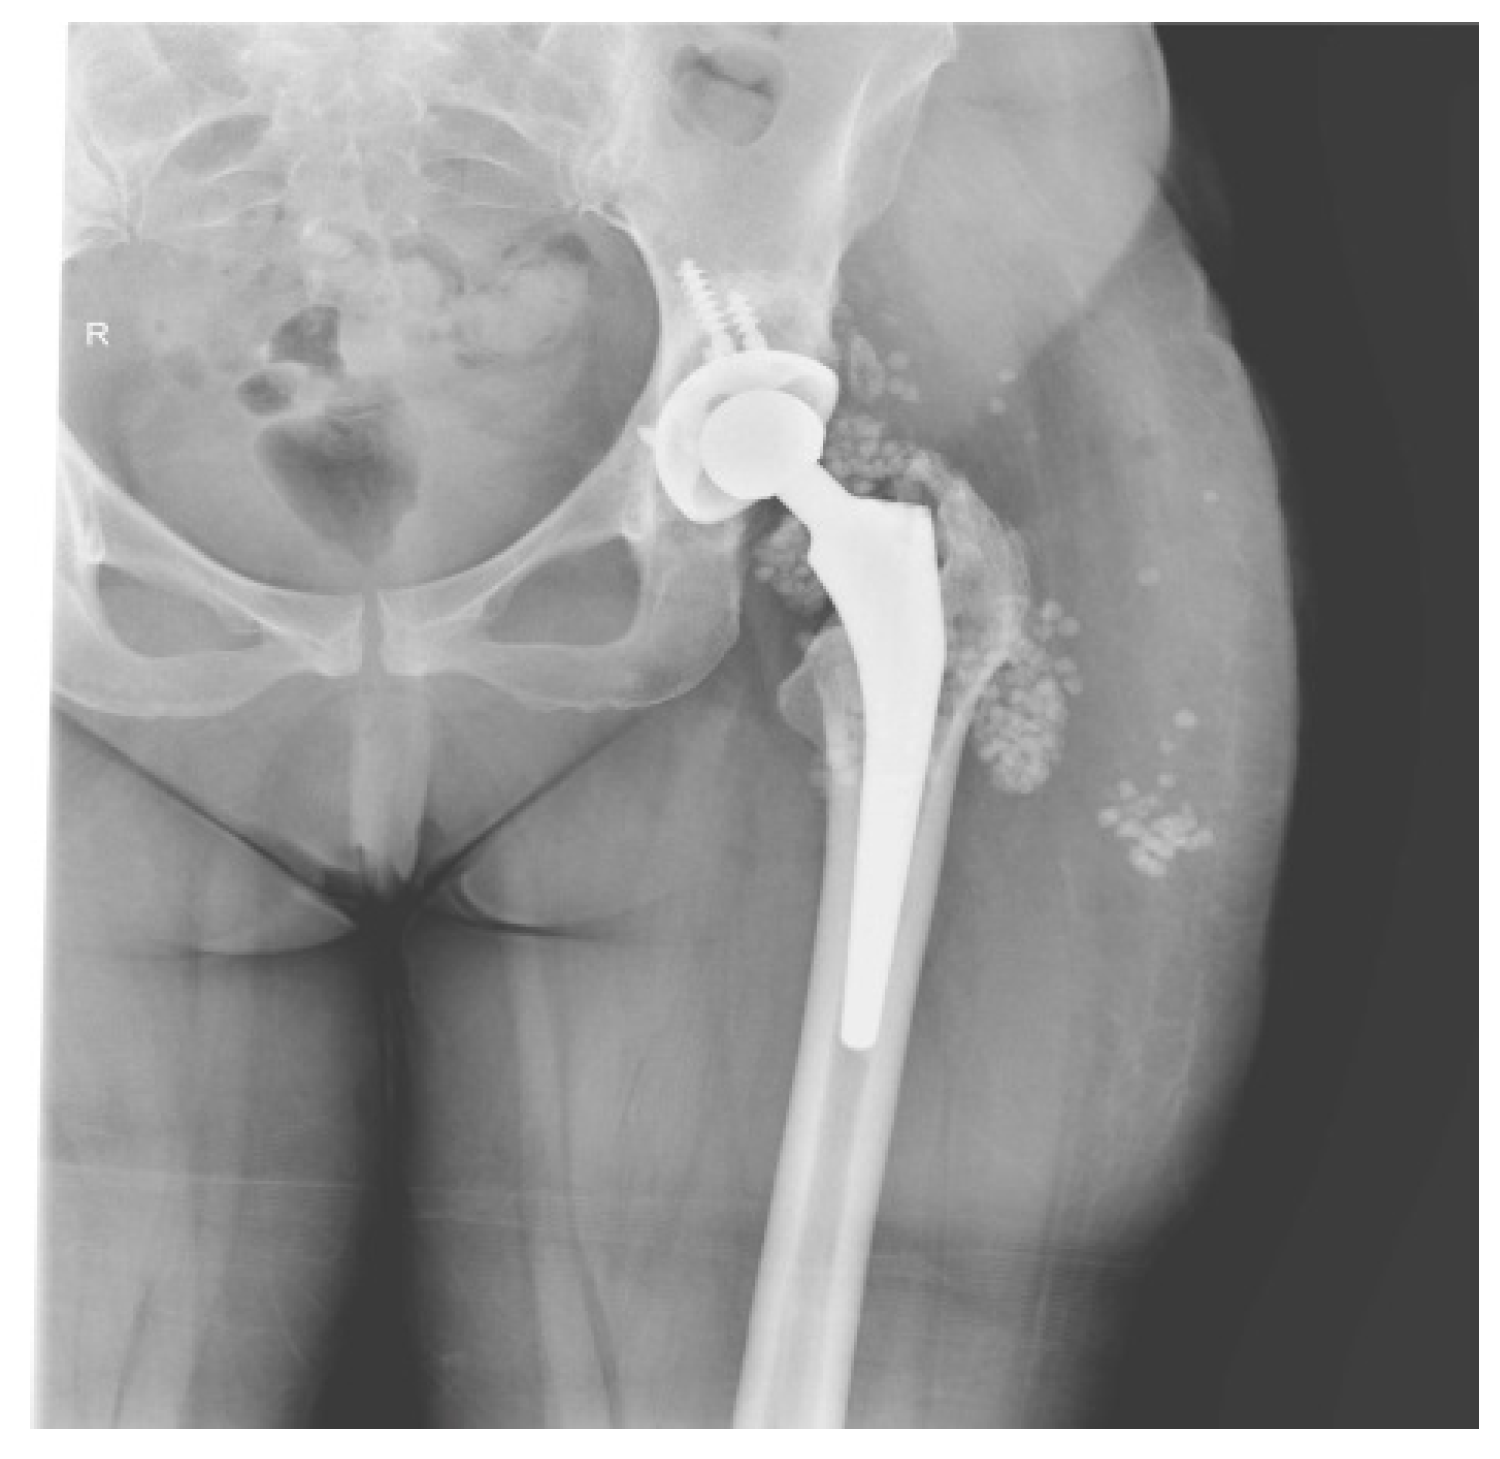

2.1. CASE 1

2.2. CASE 2